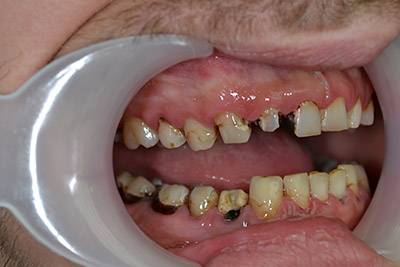

10. eset

Savas kémhatású anyagok, mint például a szénsavas üdítők túlzott használata is a fogak zománcrétegének nagyfokú károsodását okozhatják. 35 éves férfi páciensnek készítettünk a frontfogaira Zirkon koronákat, a rágófogaira pedig fémkerámia szóló koronákat. 28 koronával állítottuk helyre a fogazatot.